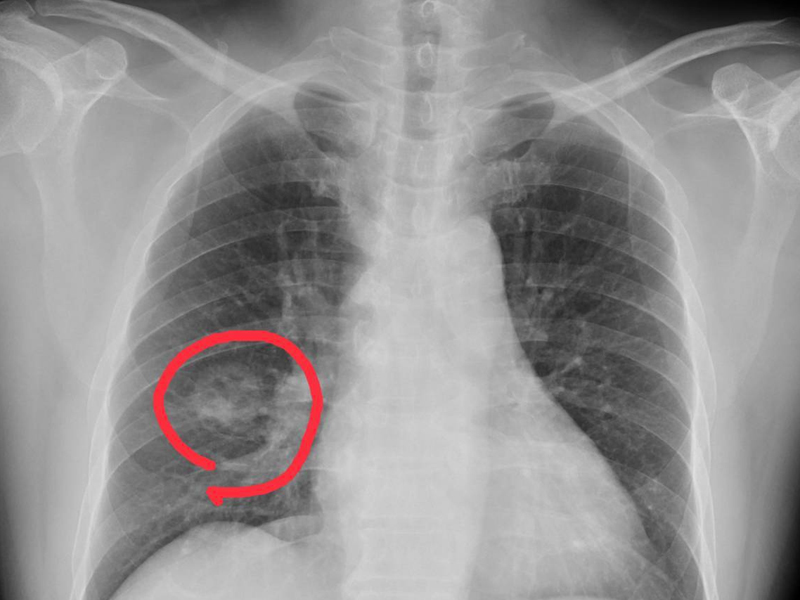

1. 嚴重胸痛

疼痛反應是猝死的發病徵兆中,最易被我們抓住和感知的信號。

當感到胸部劇烈、緊縮、壓榨性的疼痛,且感到透不過氣時,就要趕緊撥打醫院急救電話!